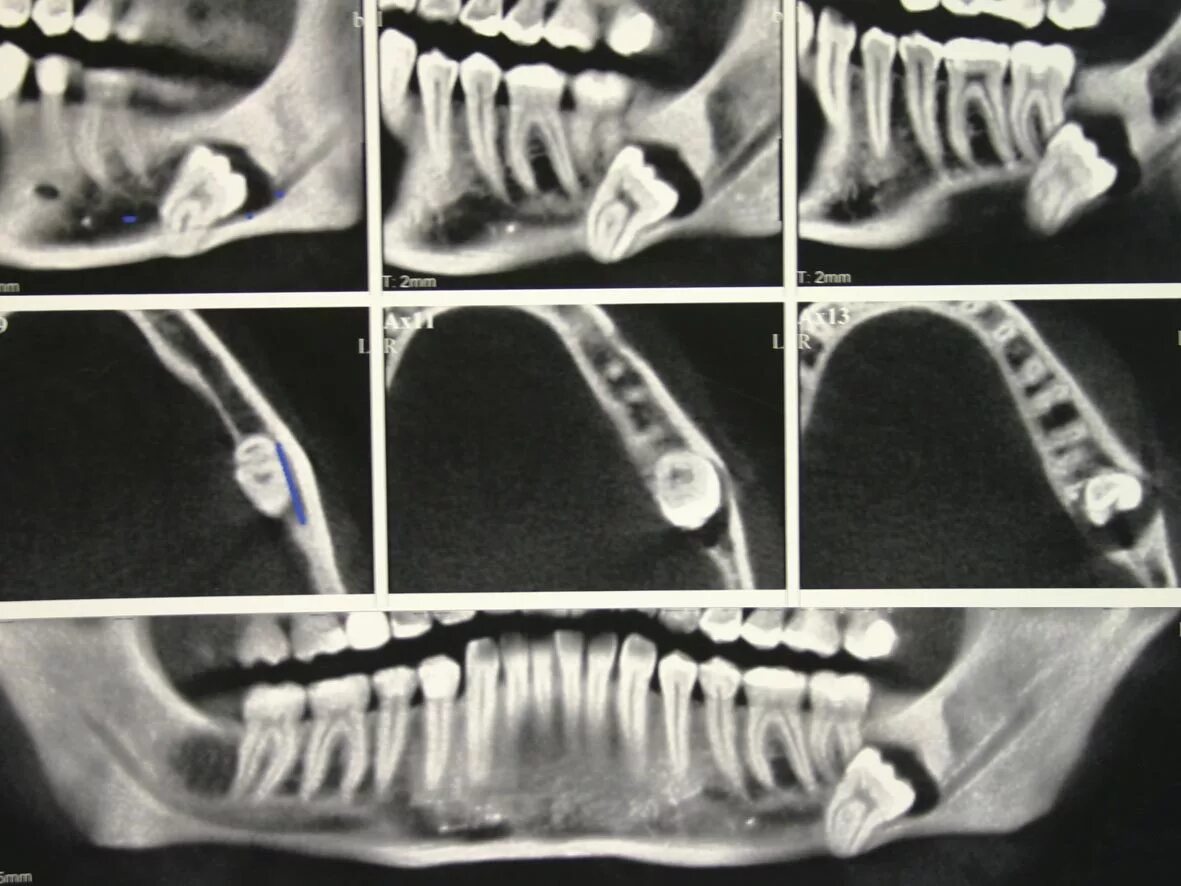

Удалить зубы семерки